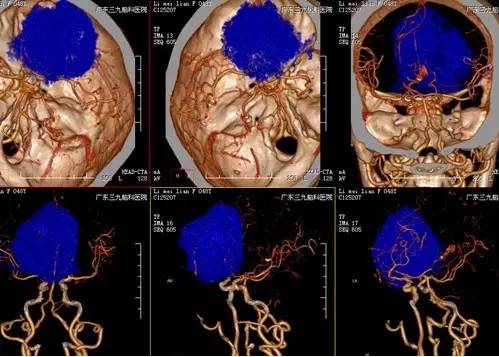

李女士,48岁,3年前开始出现间断头痛,能自行缓解,近20天头痛加重无法忍受,遂来我院门诊就诊,CT提示右侧额部类圆形稍低密度影,入院后完善检查,MR示右侧额部镰窦旁旁巨大脑膜瘤,病灶大小约7.0cm*5.9cm*6.4cm,CTA提示肿瘤周围血管包绕,血供丰富。患者手术由神经外一科主任张良主刀完成,行全麻下右侧额部镰窦旁巨大脑膜瘤切除术,术后患者症状消失,目前恢复良好出院。

脑膜瘤是颅内最常见的良性肿瘤,一般将最大径大于7.0cm的脑膜瘤称为巨大脑膜瘤。手术是治疗颅内巨大脑膜瘤的最佳方法,应争取做根治性全切除手术,以减少复发。巨大脑膜瘤血供丰富,常与颅神经、大动脉、海绵窦等粘连,或侵犯静脉窦等,手术难度大,风险高,致死致残率高。本例患者病变与大脑镰窦关系稍密切,病灶大小约7.0cm*5.9cm*6.4cm,其内示多发小血管穿行;病灶局部突入额部板障内,病变范围颅骨变薄,板障血供丰富,术中去除颅骨时出血较多。术中应用显微操作,仔细分离肿瘤周围的大脑前动脉,保护嗅神经,尽量减少了脑组织不必要的牵拉。由于肿瘤浸润矢状窦,手术时切除累及的矢状窦和大脑镰,做到肿瘤一级切除。术后患者一般情况良好,密切监测颅内压力变化及病情变化,术后有一过性发热,未有明确神经功能障碍及并发症,恢复良好出院。